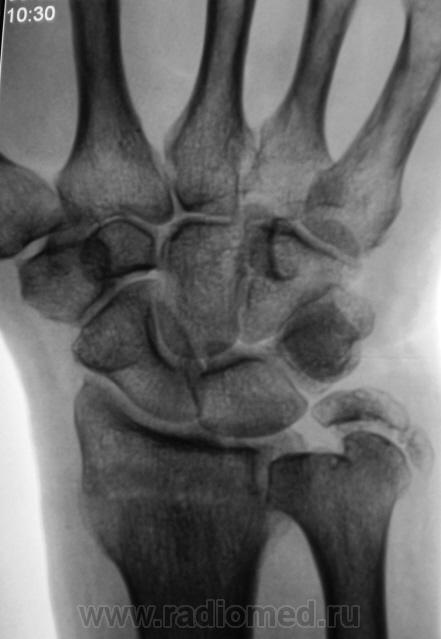

Травма.

Вот еще одна непонятность.

А линия просветления в метаэпифизе луча?

Контур нечеткий, склероз и т.д.-на перелом не схоже. А действительно локальная болезненность в латер. лодыжке?

Да, болезненность есть, клинически хирурги - за перелом.

Краевой перелом Наружной лодыжки